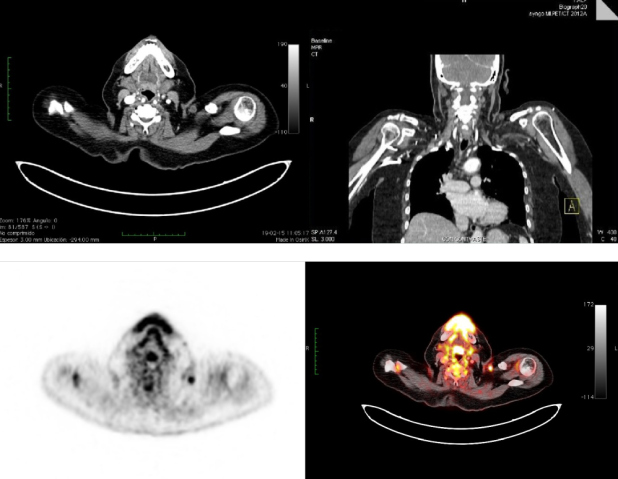

Se realiza PET-CT de etapificación con 18F-FDG, donde se observa un nódulo subcutáneo sólido de 11 mm, bien delimitado, condensidad de partes blandas, ubicado en hombro izquierdo adyacente a la articulación acromioclavicular. Se evidencia aumento del metabolismo glucídico (SUVmax = 3,2) (Fig. 2) y una adenopatía supraclavicular ipsilateral de 15 mm, hipermetabólica (SUVmax = 3.5) (Fig. 3). El resto de la exploración no mostró lesiones hipermetabólicas (Fig. 4).